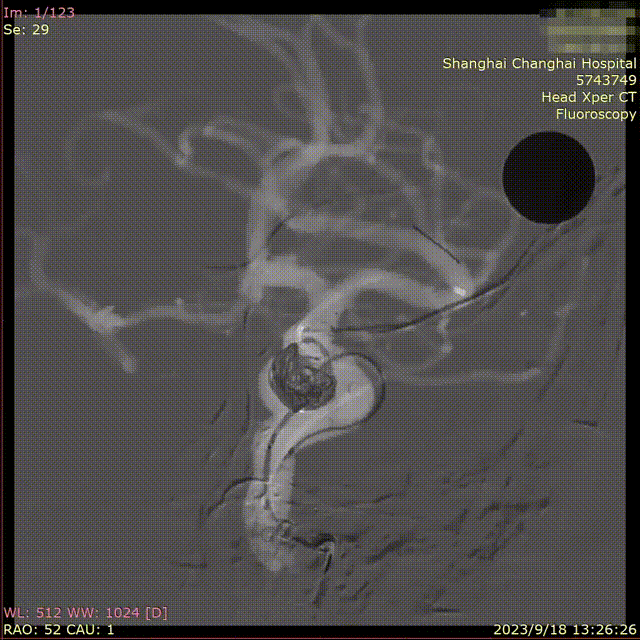

后在动脉瘤囊内陆续填塞3枚Nufairy™弹簧圈,并完全释放支架,造影提示动脉瘤大部分栓塞,瘤腔内造影剂明显淤滞,载瘤动脉通畅,远端血管未见明显异常,覆盖分支血管部位眼动脉,分支血管状态畅通。

图片

观察20min后复查造影,情况同前,查头颅Dyna CT,未见出血。